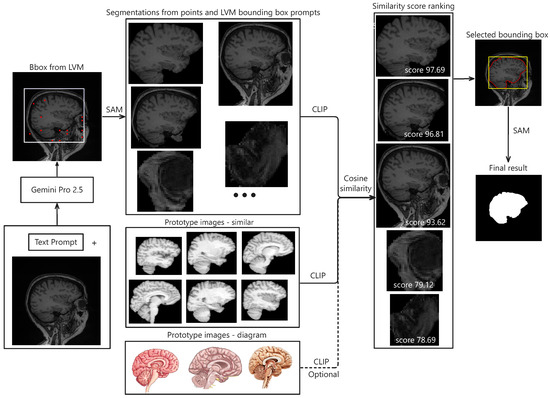

The proposed pipeline begins with prompt-engineered Gemini Pro to estimate precise bounding boxes for the target anatomical structure. From these bounding boxes, SAM is used to generate segmentation candidates by point prompting within the predicted region, while an additional candidate is generated directly from the initial Gemini-derived bounding box. Candidate selection is performed using CLIP, which computes similarity scores against a prototype embedding derived from multiple representative segmentation masks. The whole process is depicted in Figure 1.

Figure 1. Illustration of segmentation results using the proposed framework. The pipeline begins with an input image and a corresponding text prompt, which are packaged and sent to Gemini Pro 2.5 via its API. The model returns bounding box coordinates indicating the estimated target region. Within this region of interest (ROI), a set of evenly spaced points, along with the bounding box, are used as prompts for the SAM model to generate candidate segmentations. Each candidate is embedded using CLIP. Separately, prototype embeddings are computed by averaging embeddings from similar ROIs or target diagrams across various datasets. These prototypes are then compared to the candidate embeddings to compute similarity scores. The segmentations are ranked based on these scores, and the top-ranked result is selected. Finally, a refined bounding box derived from this selection is used to generate the final segmentation via SAM.